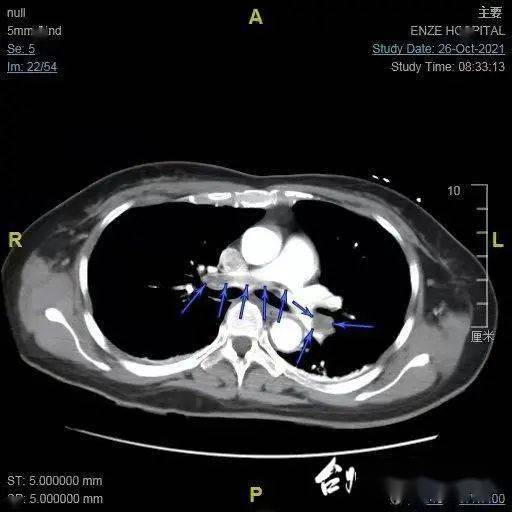

进一步检查验证了医生们的判断 。 2号的两侧肺动脉主干血管 , 80%-90%都被血栓堵住了 。 她的两条腿 , 不仅静脉曲张处有血栓 , 从膝盖以下的深静脉也聚集了大量血栓 。

文章图片

肺栓塞(资料图)